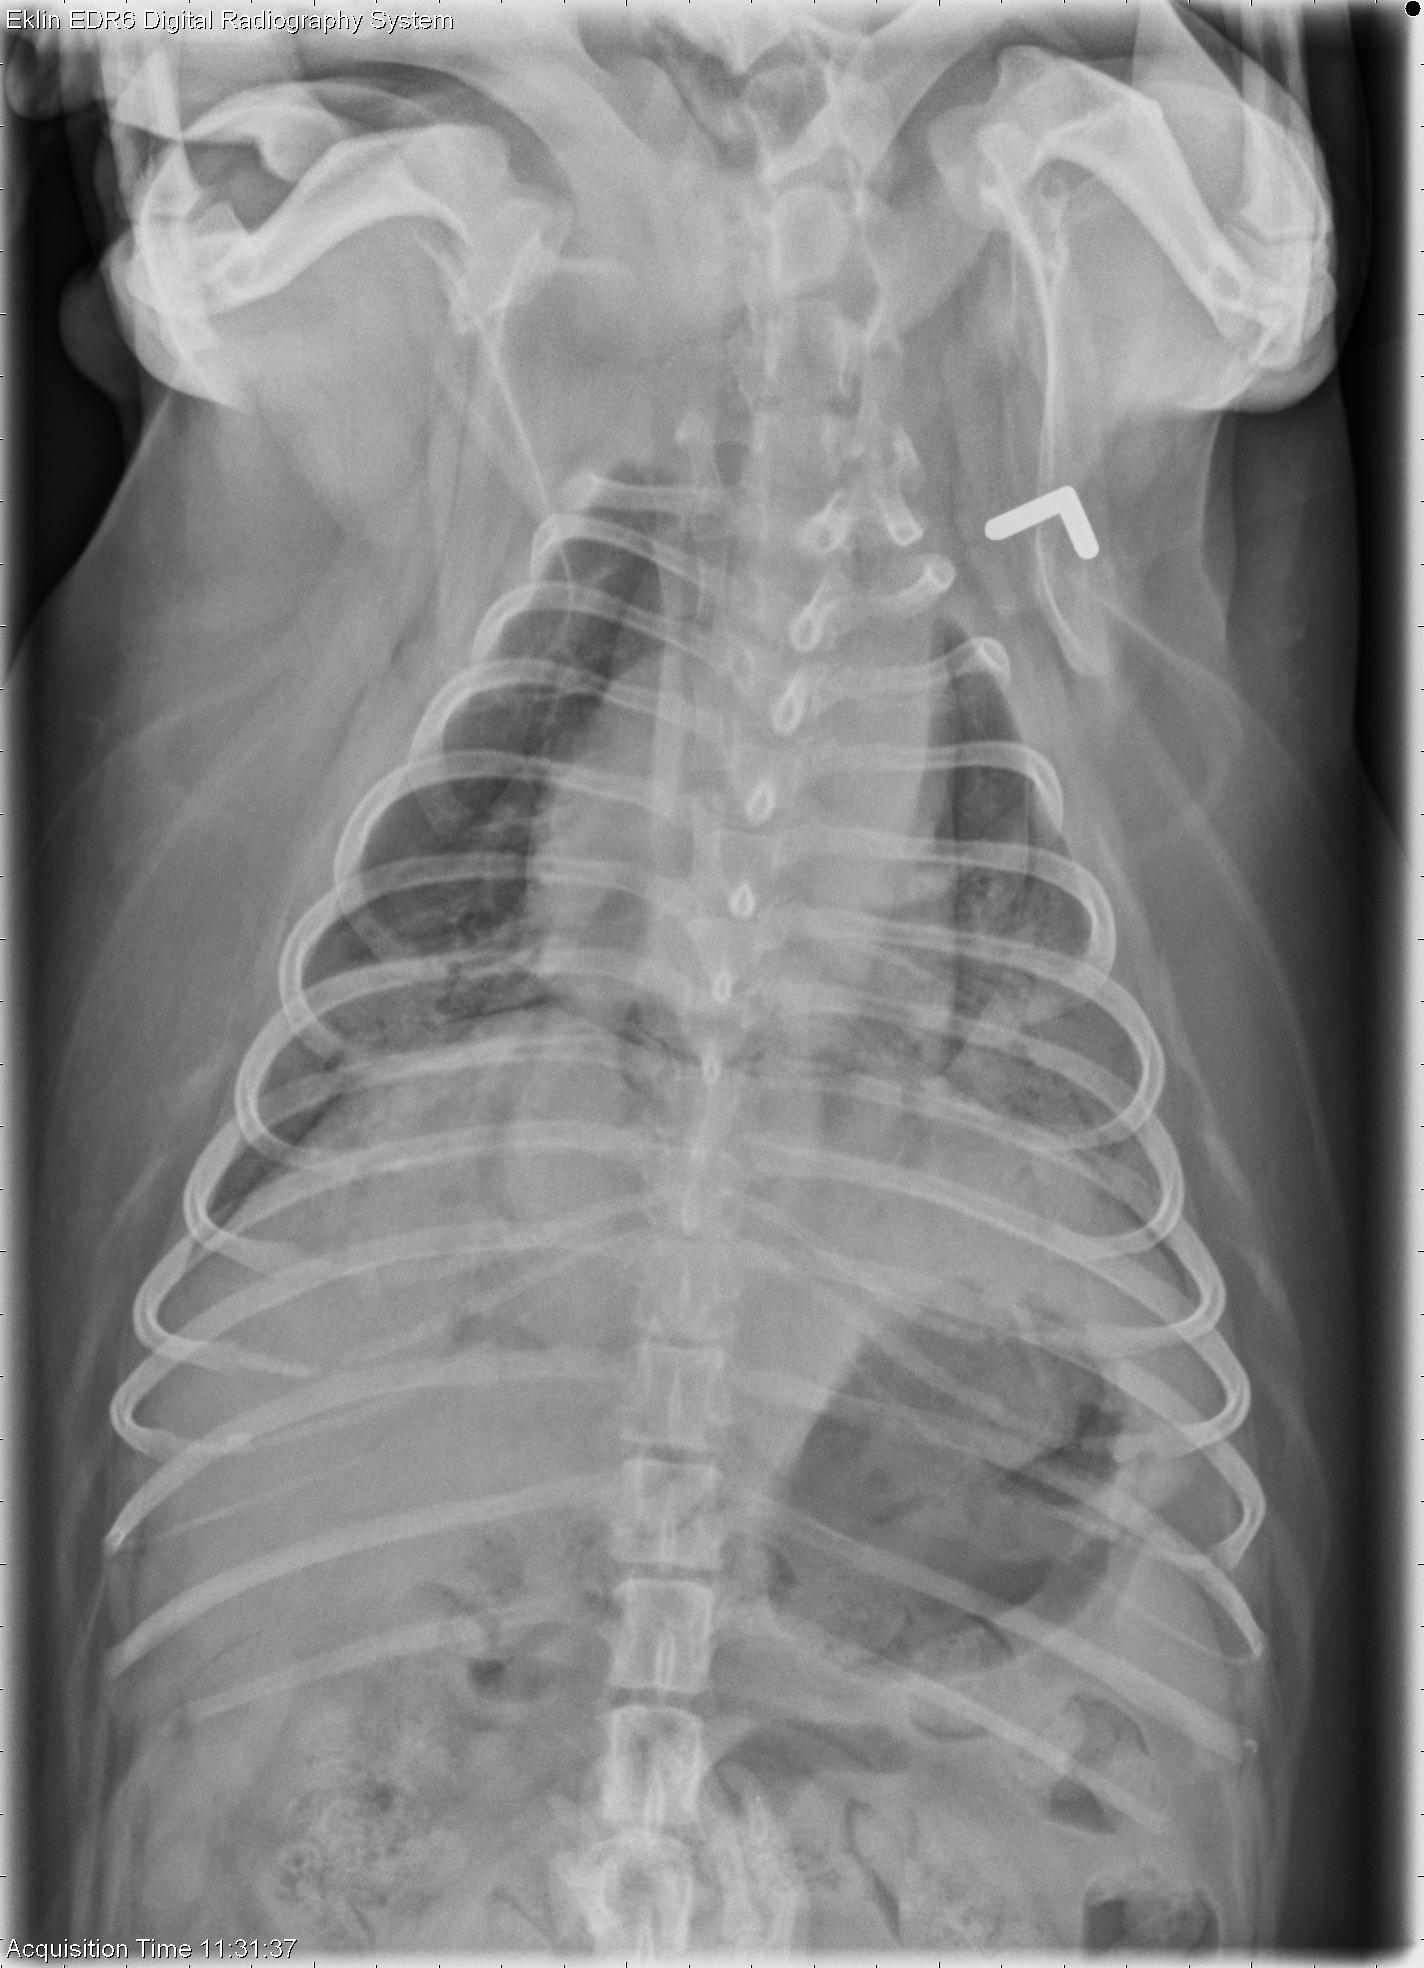

This week’s case is an 8-year-old female neutered Pug with pancreatitis. Developed increased respiratory rate and crackles while hospitalized.

DV Thorax

The cardiac silhouette is normal in size and shape. The pulmonary vasculature is normal. There is a moderate interstitial to alveolar pulmonary pattern in the left and right caudal lung lobes, causing increased soft tissue opacity and faint air bronchograms. The pleura and mediastinum are normal. No abnormalities are seen in the musculoskeletal structures.

The most likely diagnosis for the pulmonary pattern is non-cardiogenic pulmonary edema (ARDS) secondary to pancreatitis.

Histopathology of the lungs showed diffuse alveolar capillary hemorrhage and fibrin deposition consistent with ARDS.